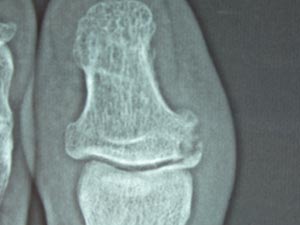

「そんなら、もしかしてこっちもですか。」と右足の第2指(ひとさしゆび?)も診てもらう。こっちはもっとひどい。木っ端みじんになっている。もうかれこれ30年ほど曲がったままで、少し痛い。

「珍しいから、また見せに来てください。私も調べておくから。」と言うことになった。ウ〜ム、大きな病院で診てもらった方が良いかも。